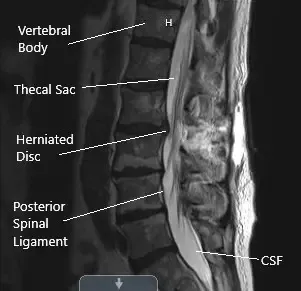

Postoperative sagittal MRI section of the lumbar spine showing laminoforaminotomy.

After removal of all loose fragments, irrigation of the surgical wound was performed. Far lateral decompression was checked and laminectomy and foraminotomy were completed. The right L3 nerve root was thoroughly decompressed.